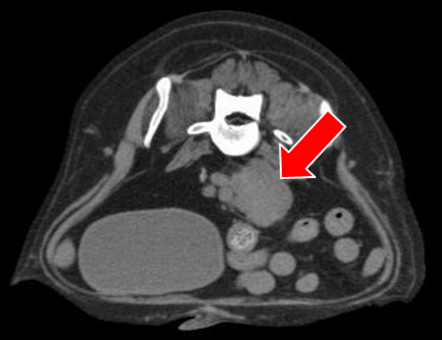

CT(第2病日)

肝動脈尾状葉枝が栄養血管門脈血の流入は確認されず

尾状葉由来5cm大

動脈相

門脈相

CT MIP

【診断・治療方針】

腹腔内腫瘤の破裂による非外傷性出血

― 腹腔内腫瘤は肝尾状葉由来 (Φ5cm)

腫瘤は動脈相で早期膿染

― 肝動脈尾状葉枝が栄養血管